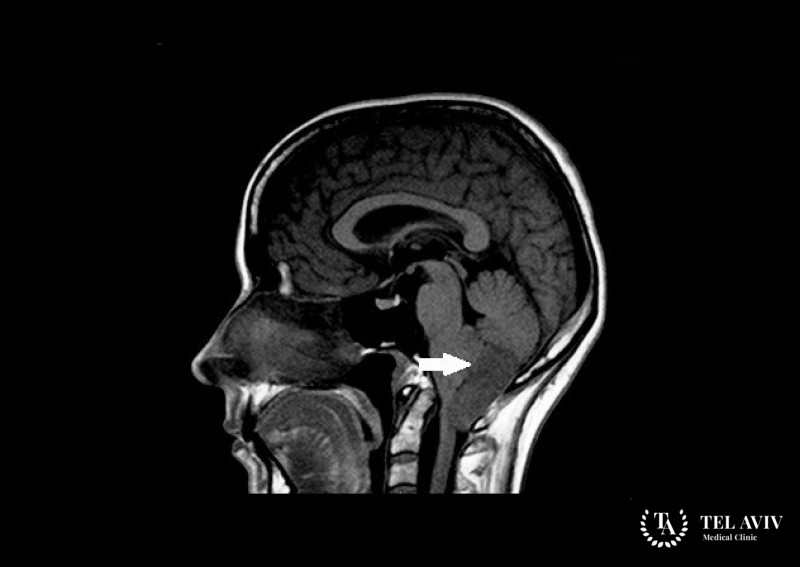

- Магнитный резонанс. Обладает максимальной информативностью в исследовании мозговых структур. На снимках отображается форма, размерность, структура эпендимомы. Четкая визуальная картина позволяет изучить сосуды головного мозга. МРТ проводится детям, взрослым, процедура полностью безопасна для здоровья;